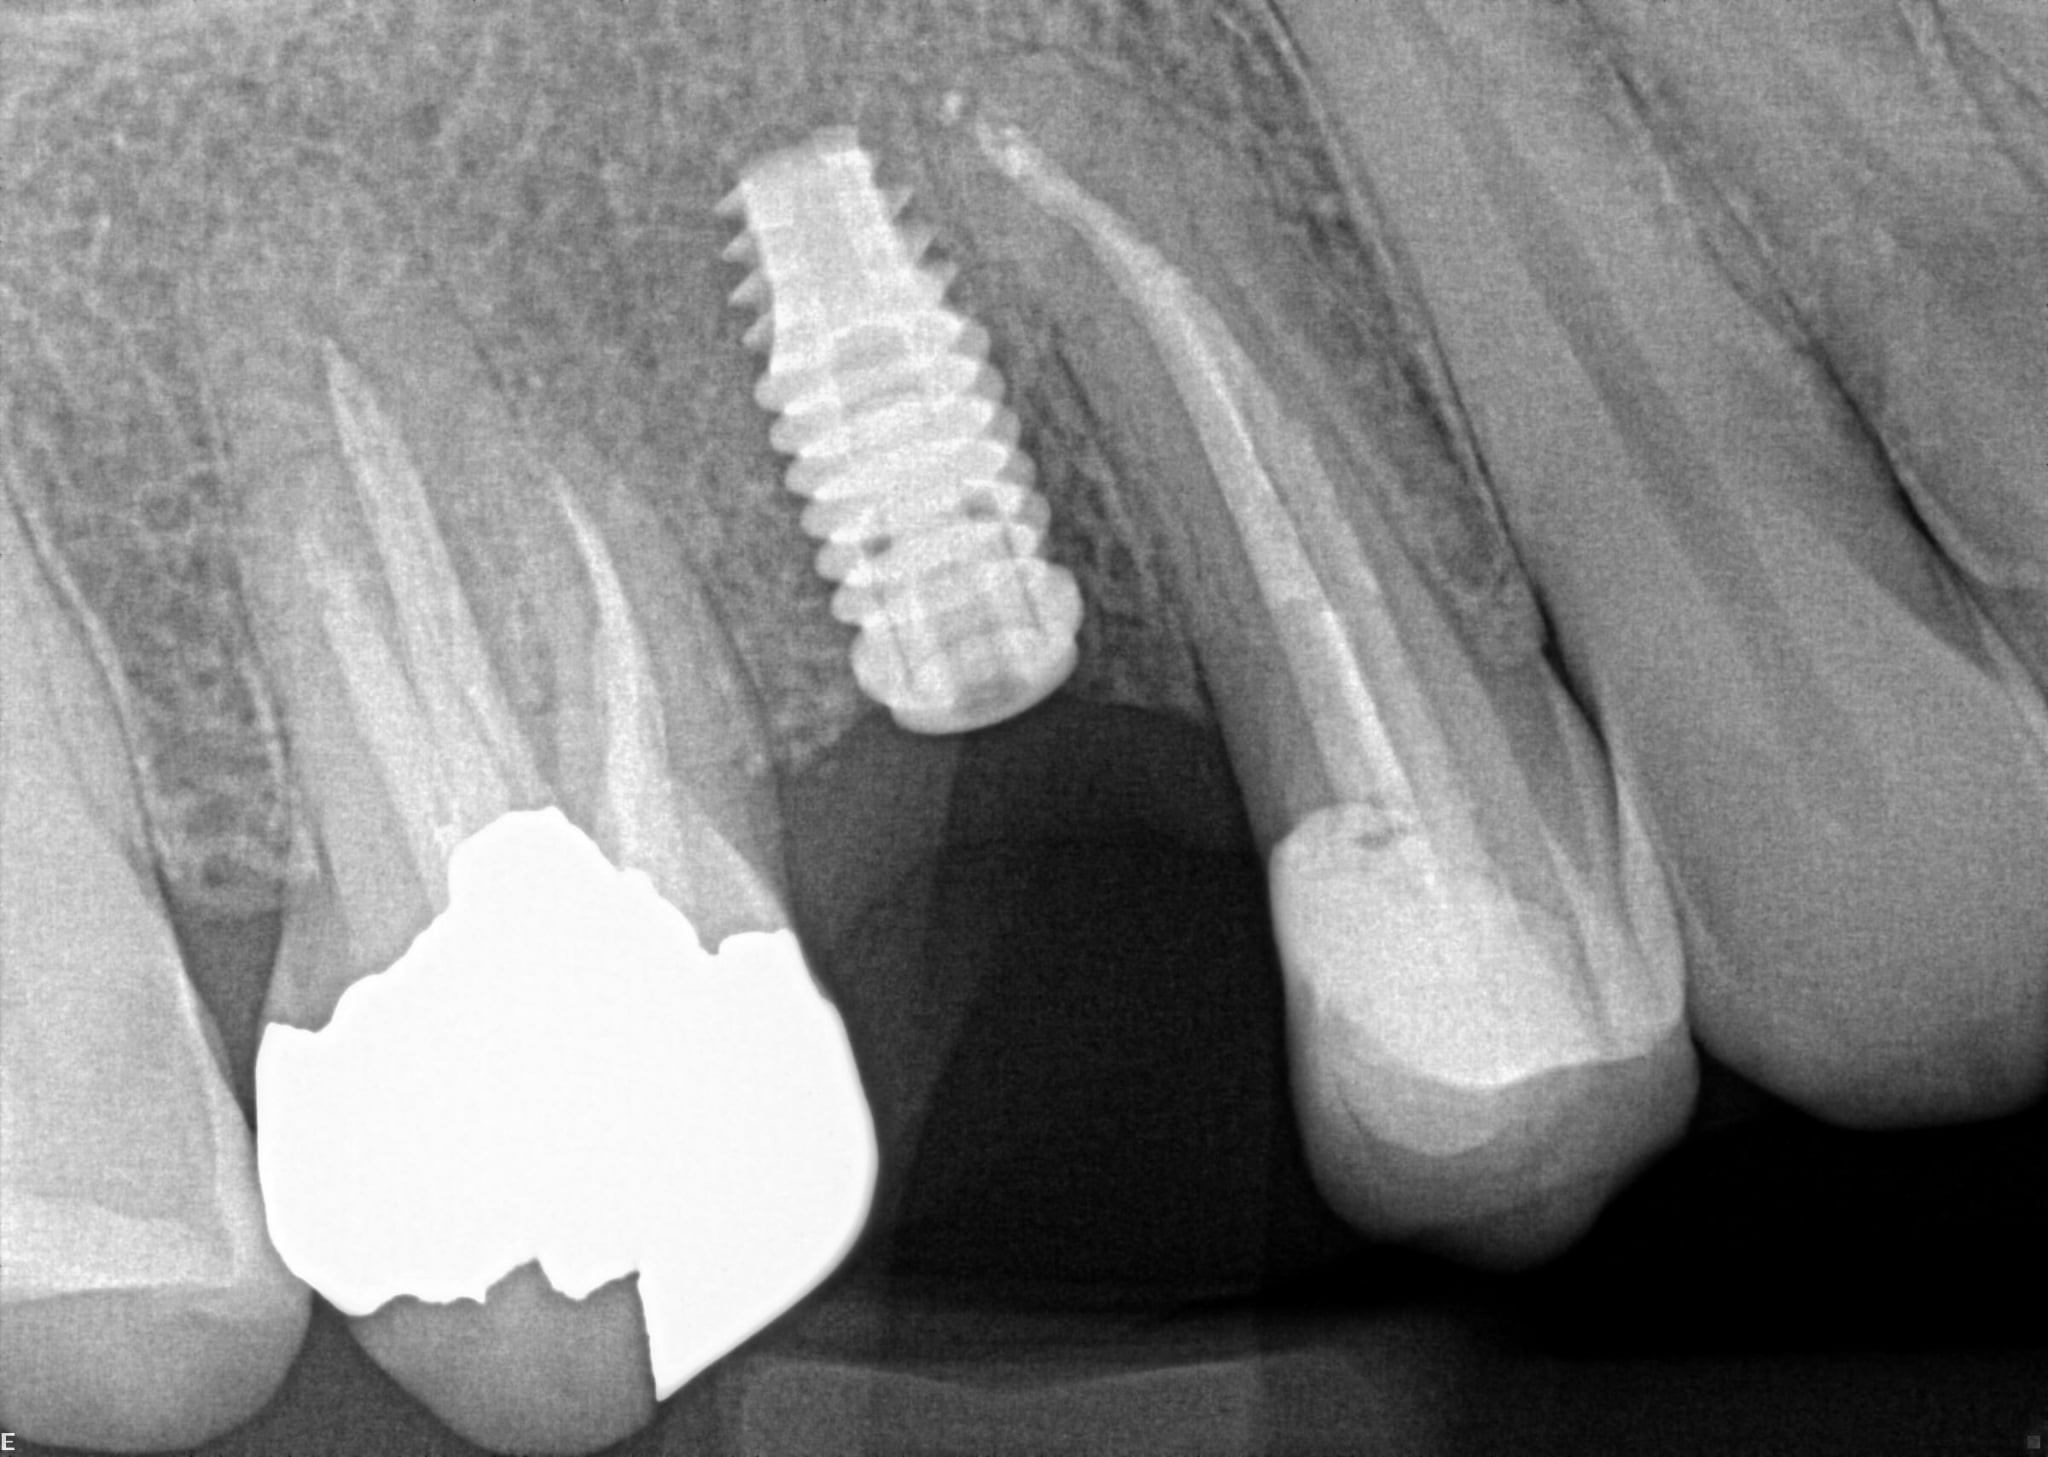

1.  What option can describe the post placement in the X ray bellow for the tooth # 2.5?